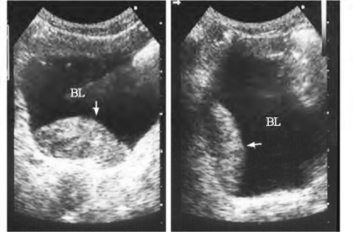

3.膀胱内血凝块显示扁平、基底较宽的中等偏强回声团块,可随体位改变而移动(图30-7)。

图30-7 膀胱凝血块声像图

左图箭头所指为平卧位膀胱内团状略强回声,右图箭头所指为改变体位后团状回声随体位改变而移动